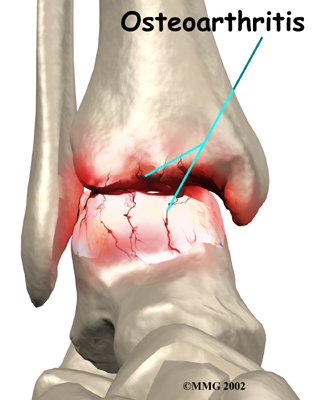

Injury to a joint, such as a bad sprain or fracture, can cause damage to the articular cartilage. The cartilage can be bruised when too much pressure is exerted on it. This damages the cartilage, although if you look at the surface it may not appear to be any different. The injury to the material doesn't show up until months later. Sometimes the cartilage surface is damaged even more severely, and pieces of the cartilage are ripped from the bone. These pieces do not heal back and usually must be removed from the joint surgically. If not, they may float around in the joint, causing the joint to catch and be painful. These fragments of cartilage may also do more damage to the joint surface.

Once this cartilage is ripped away, it does not normally grow back. Unlike bone, holes in the surface are not simply replaced by the cartilage tissue around the hole. Instead the defects are filled with scar tissue. The scar tissue that forms is not nearly as good a material for covering joint surfaces as the cartilage it replaces. It just can't support weight and isn't smooth like true articular cartilage.

Over many years this imbalance in the joint mechanics can lead to damage to the articular surface. Since articular cartilage cannot heal itself very well, the damage adds up. Finally, the joint is no longer able to compensate for the increasing damage, and it begins to hurt. The damage occurs well before the pain begins.

Pain is the main problem with arthritis of any joint. This pain occurs at first only related to activity. Usually, once the activity gets underway there is not much pain, but after resting for several minutes the pain and stiffness increase. Later, when the condition worsens, pain may be present even at rest. The pain may interfere with sleep. The joint may swell, fill with fluid, and feel tight, especially following increased activity. As the articular cartilage starts to wear off the joint surface, the joint may squeak when moved. Doctors refer to this sound as crepitation.

When OA has reached a very severe stage, the bone itself under the articular cartilage may become worn away. This can lead to increasing deformities around the joint. In the final stages, the alignment of the bones can begin to form odd angles where they meet at the joint.